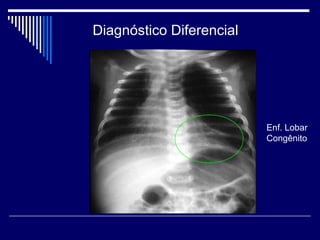

Diagnóstico Diferencial

Enf. Lobar

Congênito